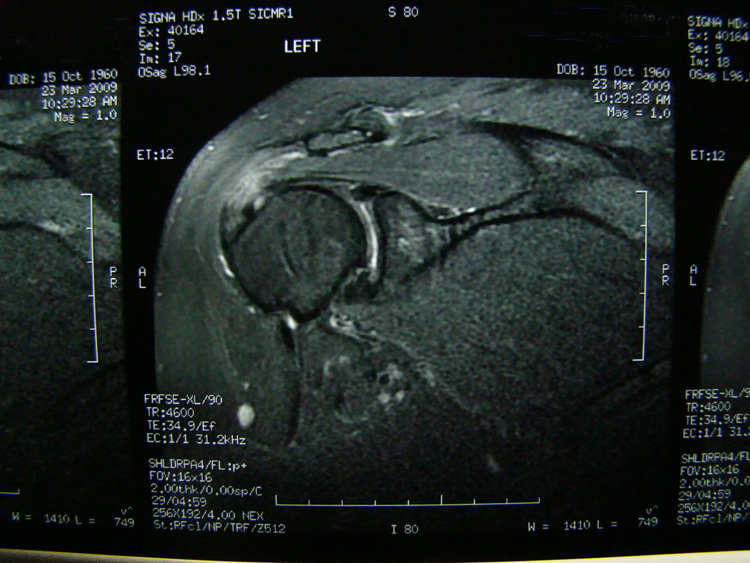

This patient presented with shoulder pain that interfered with work and exercise. The visible fluid-filled cysts on the “Before" MRIs are from chronically injured rotator cuff tendon roots.

The patient underwent treatments of a highly specialized fine-needling technique pioneered by Dr. Tallman.The follow-up MRI was done 2 months after his 6th treatment. He was released with a pain-free, full range of motion with unrestricted activities.